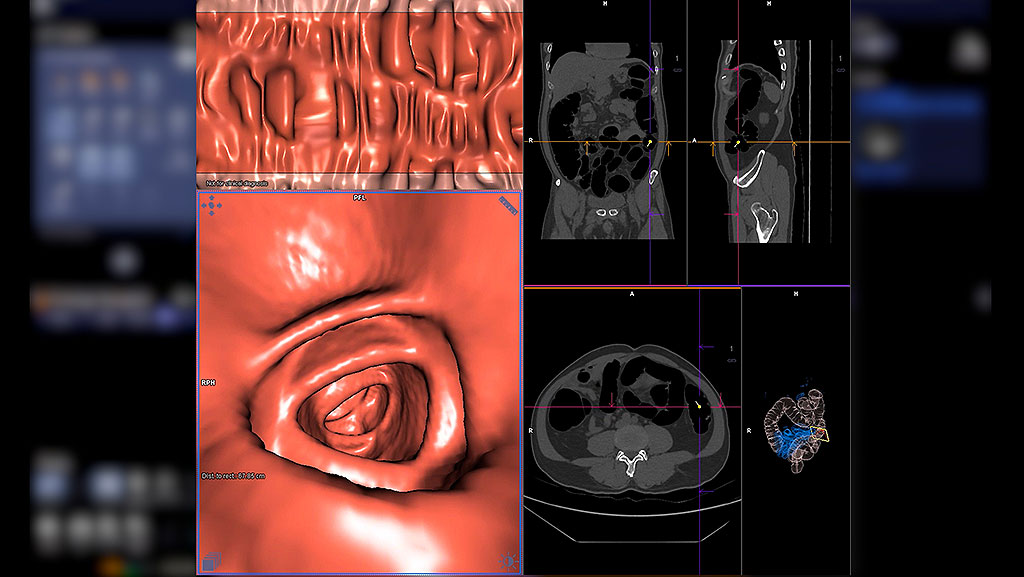

CT colonography is a medical imaging test that uses a CT scanner to visualize the inside of the large intestine (colon and rectum). It is also called a virtual colonoscopy because the images let doctors see the colon as if they were inside it, without the need for a real tube.

In a traditional colonoscopy, a doctor uses a long tube with a camera to view the colon. In CT colonography, a CT scan captures multiple X-ray images from different angles. Then a computer combines these images to create 2D and 3D views of the colon. A radiologist reviews these images to find polyps or other problems.

CT colonography (also called virtual colonoscopy) uses a special CT scan to capture many 2D and 3D images of your colon and rectum, so doctors can see inside your large bowel without inserting a long tube. These images help doctors find polyps or early signs of colorectal cancer.

What Technology Does It Uses

This test uses a CT scanner to take many X-ray pictures of your belly from different angles. A computer then builds these pictures into detailed views of your large intestine that a radiologist can review.

The CT scanner can show organs, soft tissue, and blood vessels inside your body with more detail than regular X-rays because it creates cross-sectional images.

Why This Method Works

A virtual colonoscopy gives doctors a virtual 3D view of the large intestine that may show problems like polyps or tumors that could turn into cancer. It also may reveal issues outside the colon that need attention.